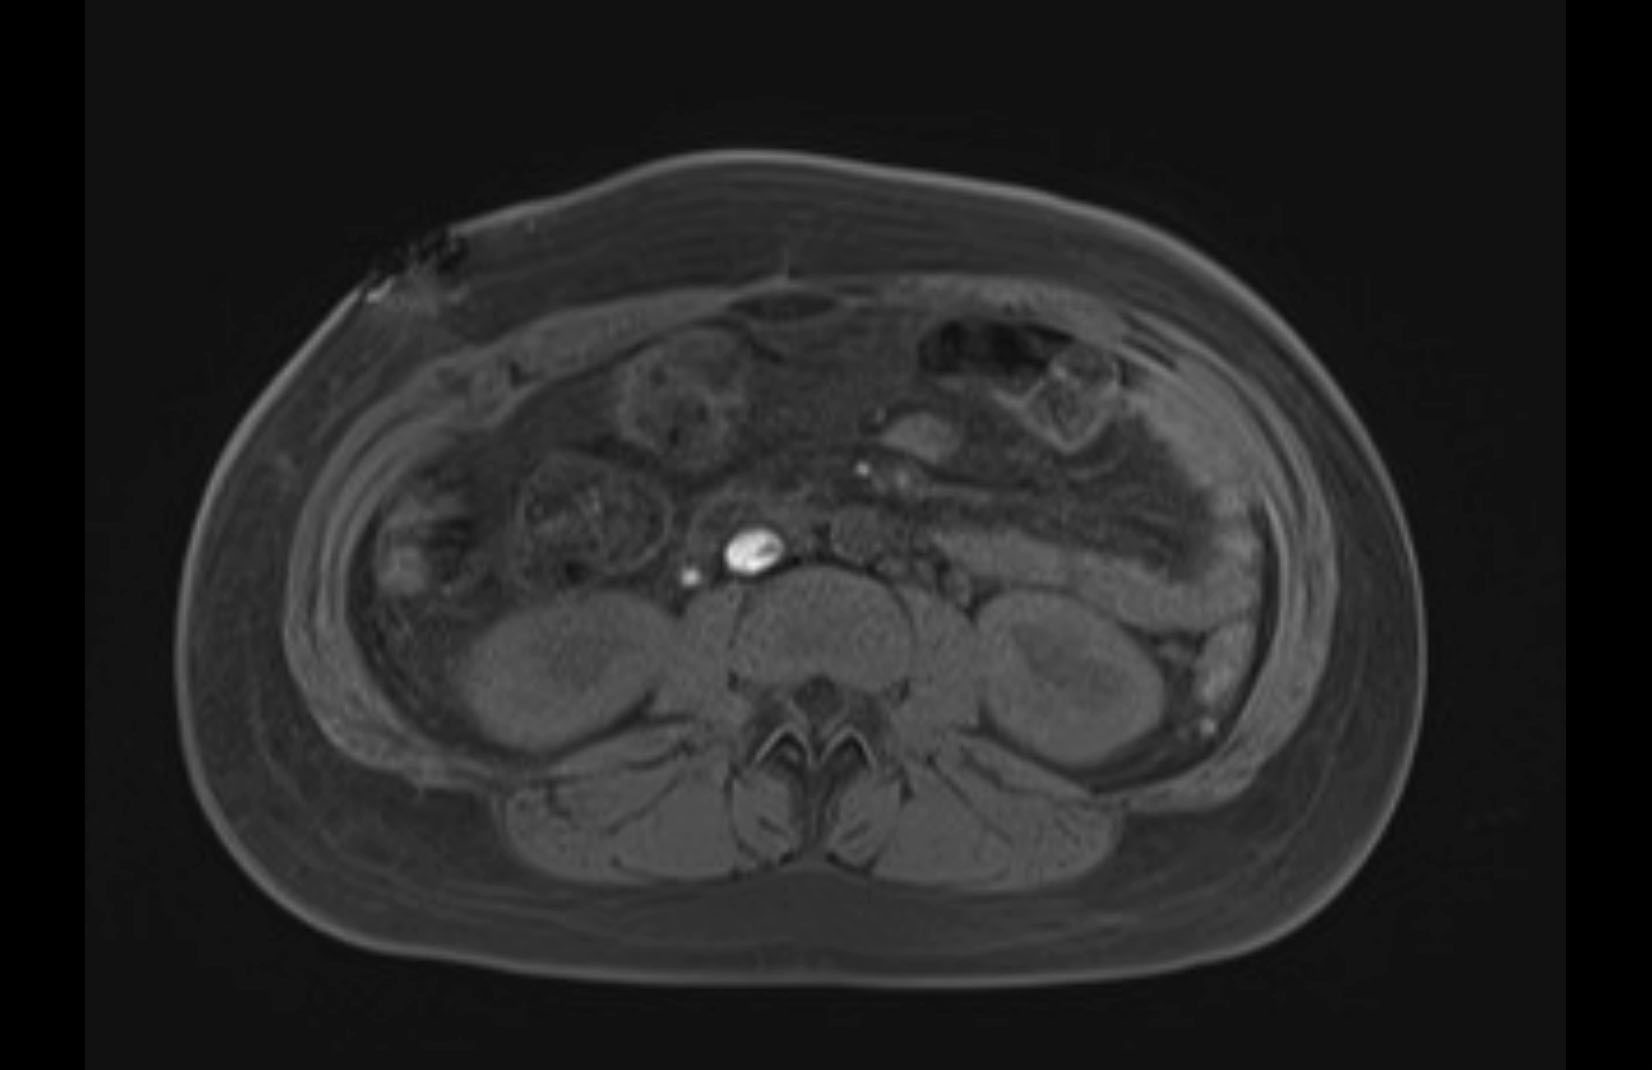

MRI T1

MRI T2